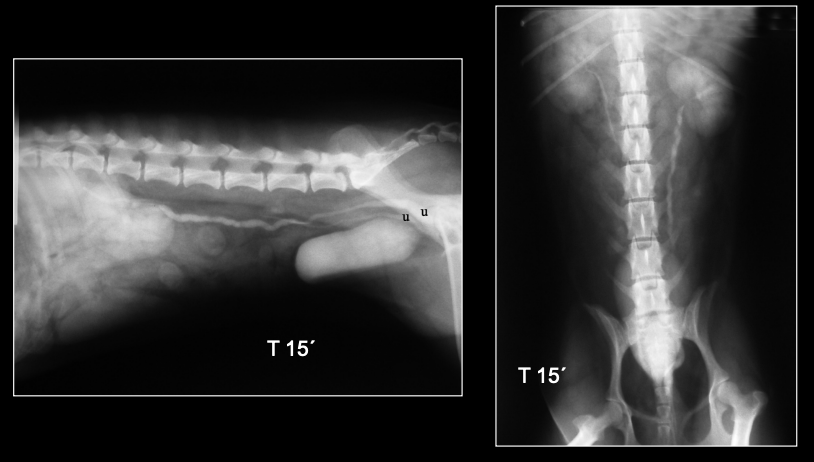

UROGRAFÍA EXCRETORA

Inyección IV de contraste yodado.

Opacificación secuencial: riñones → uréteres → vejiga.

Realizar proyecciones secuenciales.

(Imágenes: T 5’, T 15’.)